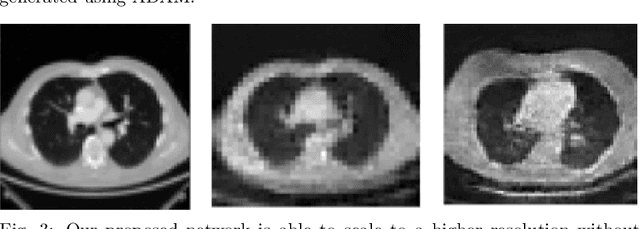

Abstract:With the advent of Deep Learning (DL) techniques, especially Generative Adversarial Networks (GANs), data augmentation and generation are quickly evolving domains that have raised much interest recently. However, the DL techniques are data demanding and since, medical data is not easily accessible, they suffer from data insufficiency. To deal with this limitation, different data augmentation techniques are used. Here, we propose a novel unsupervised data-driven approach for data augmentation that can generate 2D Computed Tomography (CT) images using a simple GAN. The generated CT images have good global and local features of a real CT image and can be used to augment the training datasets for effective learning. In this proof-of-concept study, we show that our proposed solution using GANs is able to capture some of the global and local CT variabilities. Our network is able to generate visually realistic CT images and we aim to further enhance its output by scaling it to a higher resolution and potentially from 2D to 3D.